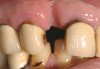

A 57-year-old woman presented seeking an implant-supported restoration to replace a failing bridge from her right maxillary second molar to her first premolar (Figure 7). Those teeth had been extracted traumatically more than 30 years ago.

Figure 7  Occlusal view before flap reflection.

Figure 7

Figure 8  Occlusal view of the severely resorbed ridge after flap reflection.

Figure 8